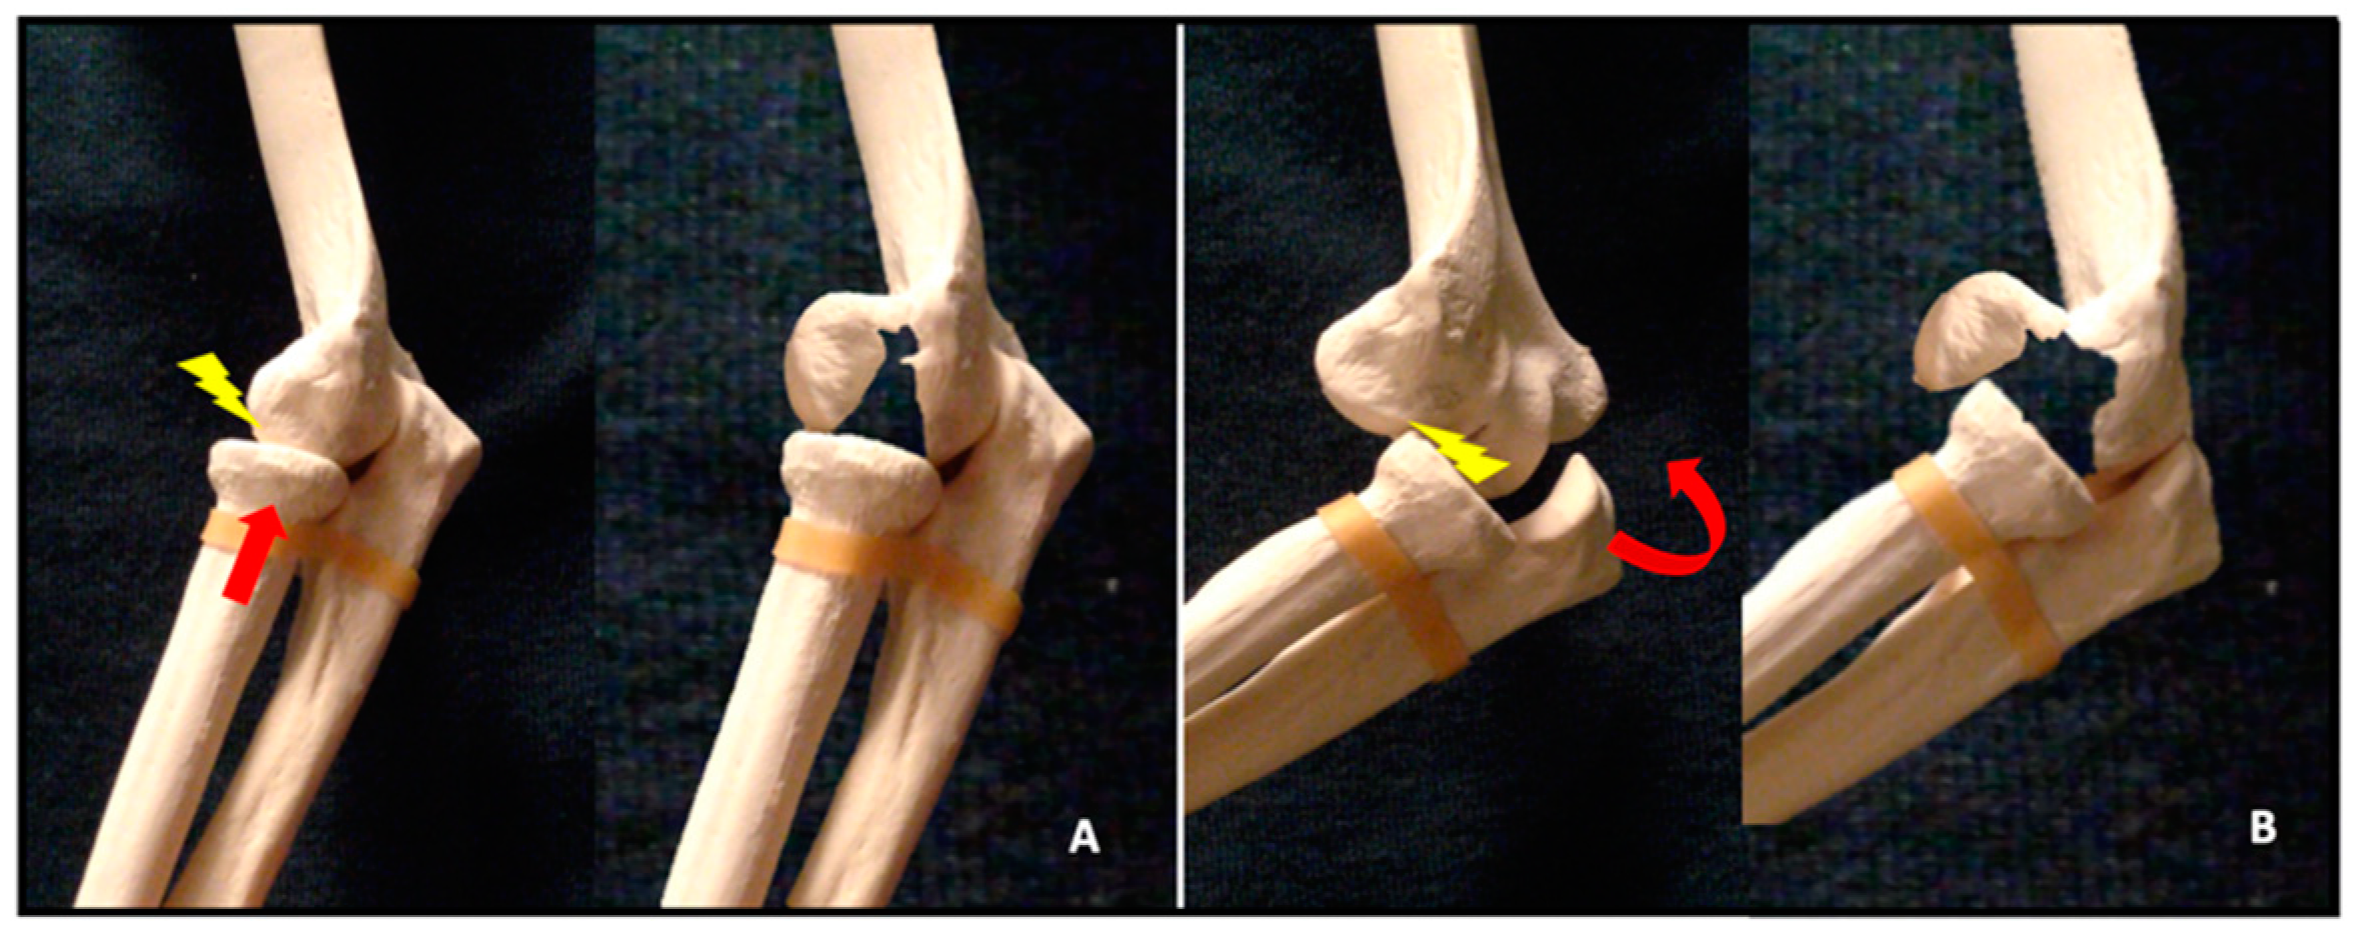

:1. Introduction